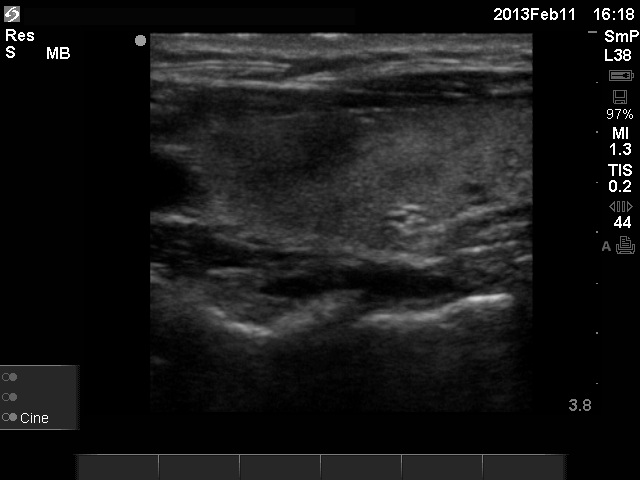

Initial examination (first row of images):

Ultrasonography: The right thyroid was echonormal and contained several small, insignificant lesions. There was a hypoechogenic lesion with blurred borders in the central and in the ventro-medial part of the left thyroid with increased intranodular blood flow.

The ultrasound pattern of de Quervain's thyroiditis and that of papillary cancer are very similar: a hypoechogenic lesion with blurred borders are found in both cases. They differ in vascularization statistically but the vascular pattern has only limited practical significance. In the acute phase of de Quervain's thyroiditis the vascularization is generally decreased but even in this case the situation was the opposite. The finding of not one but multiple hypoechogenic areas favored the possibility of subacute thyroiditis.